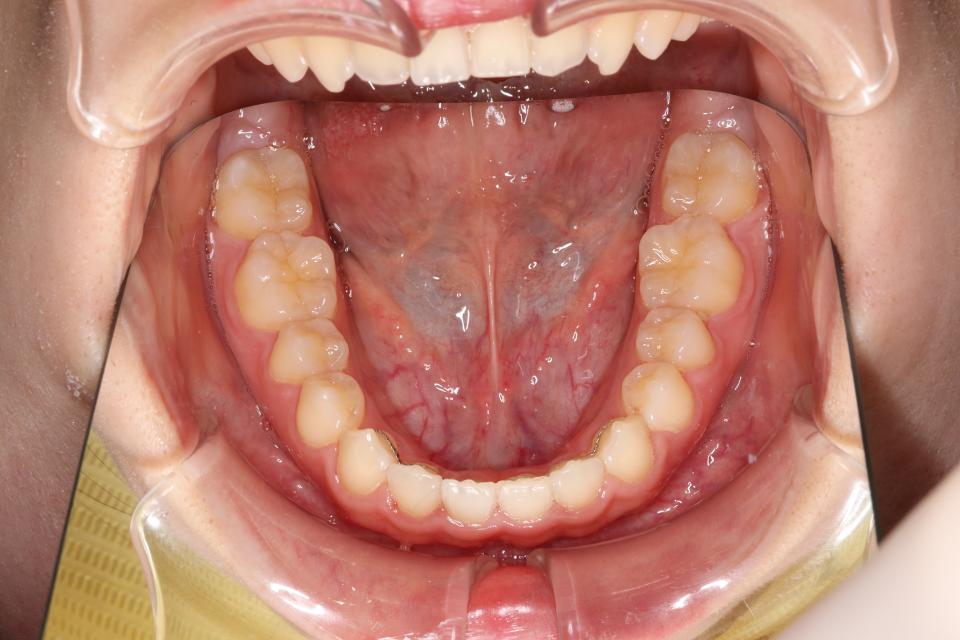

矯正治療後

20代女性の患者さんです。

上下の真ん中がズレているを気にして来院されました。

上下の歯にワイヤー(マルチブラケット装置)をつけて治療しました。

きれいに並びきるために歯のやすりがけ(IPR)も行っています。

歯並びを並べる治療は終わり、

取り外しのできる装置をはめることで後戻りの防止をして

定期的にチェックをしています。